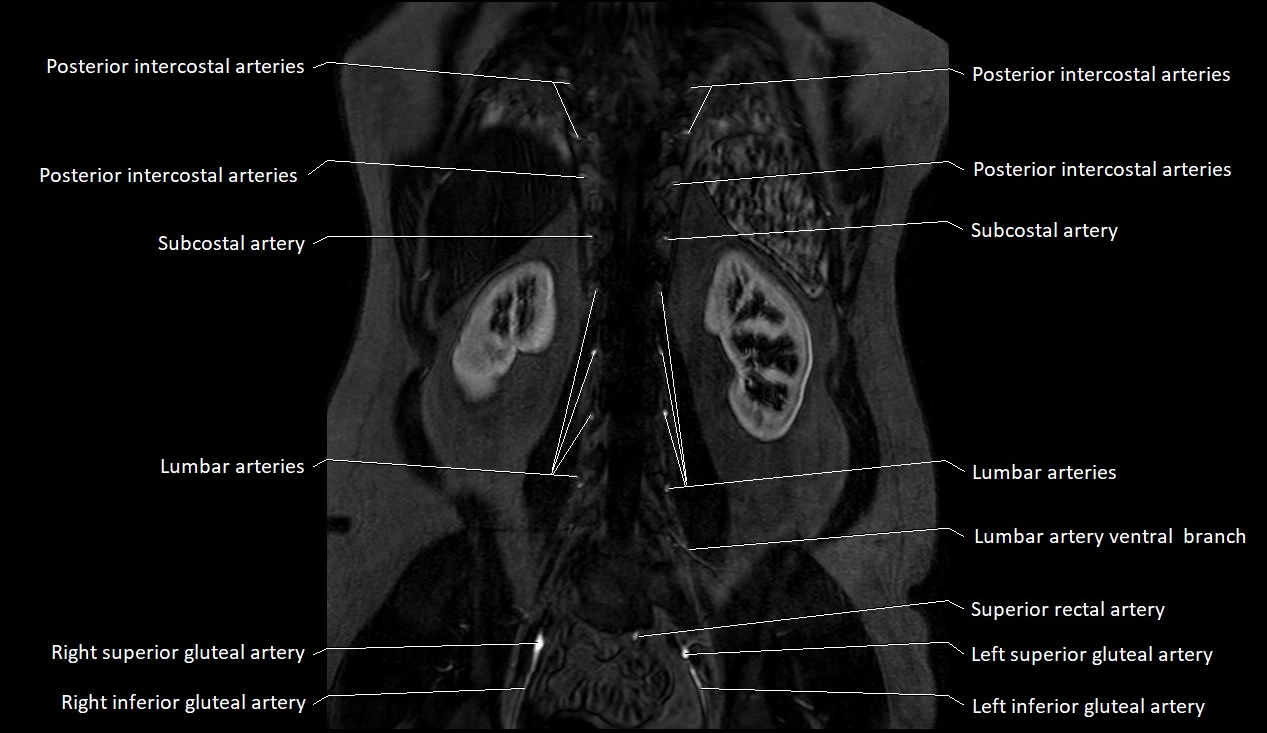

MRA (Magnetic Resonance Angiography):

• Contrast-enhanced MRA provides high-resolution imaging of the aorta and its branches

• Allows 3D reconstruction of visceral, parietal, and terminal branches

• Excellent for evaluating aneurysm size, dissection flap, stenosis, or preoperative planning

• Non-invasive alternative to conventional angiography